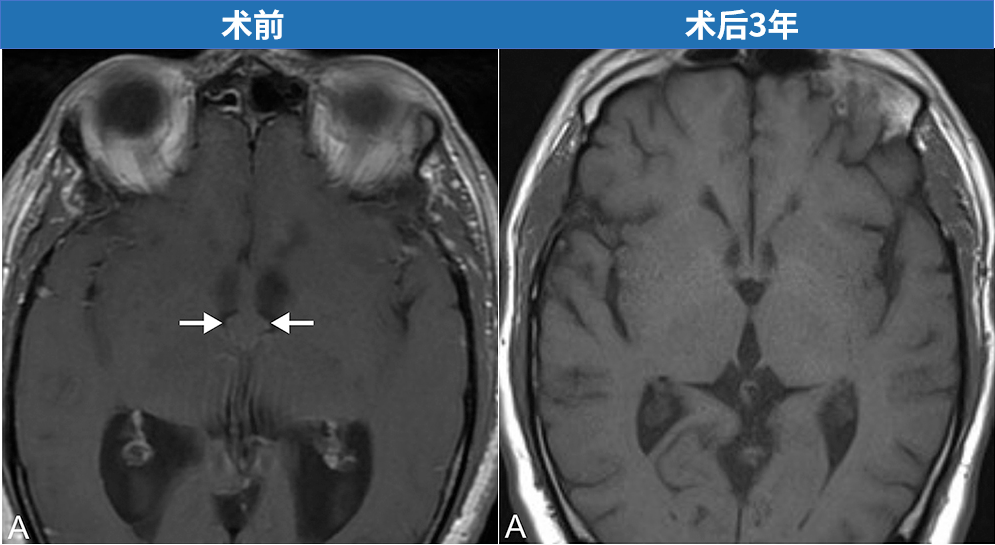

55岁男性患者因进行性行走障碍和记忆力减退就诊,影像学检查确诊为第三脑室胶样囊肿伴梗阻性脑积水。世界神经外科学会联合会(WFNS)内镜委员会前主席Henry W.S. Schroeder教授主刀施行神经内镜下囊肿切除术。术后三年随访显示囊肿完全切除,无复发迹象。

术后使用30度及45度诊断性内镜检查脑室系统,确认无残留病灶。术区用明胶海绵填塞,严密缝合帽状腱膜,皮肤采用无创伤缝线连续缝合。